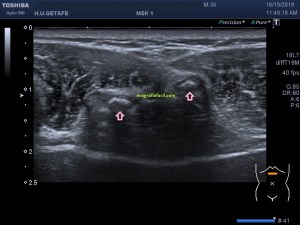

En la imagen 3 ves una imagen de un lipoma, mide 7 cms, la huella de la sonda mide 5cms, la «panoramic view» posee una regla centimetrada que sigue el contorno de la imagen, justo en la profundidad de la misma y lo marca la flecha amarilla. La profundidad la marca la flecha roja y la flecha blanca marca el rango centimetral de los 5cms, fíjate que la línea blanca es ligeramente mayor cada 5 cms. Sirve de referencia, como en la imagen 4 donde ves una colección en el glúteo de más de 10 cms.